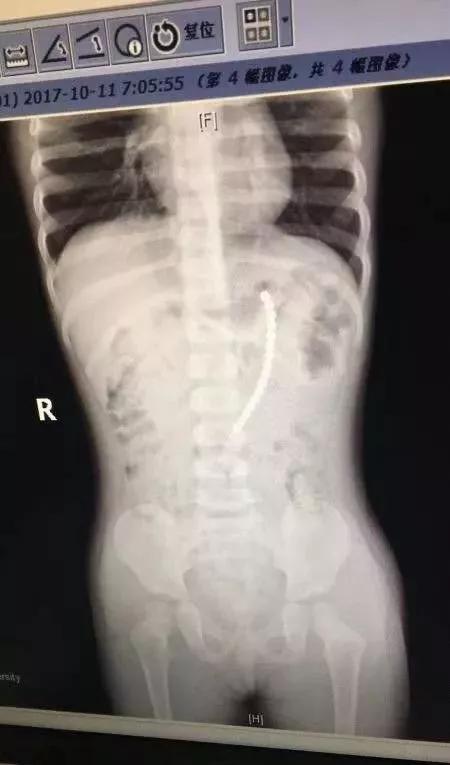

上海一个二胎家庭,父母给7岁的老大购买了一套巴克球,没想到,一天奶奶发现二宝正把一颗巴克球往嘴巴里放。奶奶吓坏了,急忙送医。通过拍片发现,竟然一共有19颗珠子在二宝体内!!其中一排珠子已经穿出胃壁,到外面去了。也就是说,孩子肠子和胃,都被巴克球穿孔了!万幸的是,这个2岁女孩吞珠后还算送医及时。医生取出珠子后,再把小女娃的胃和小肠补上。